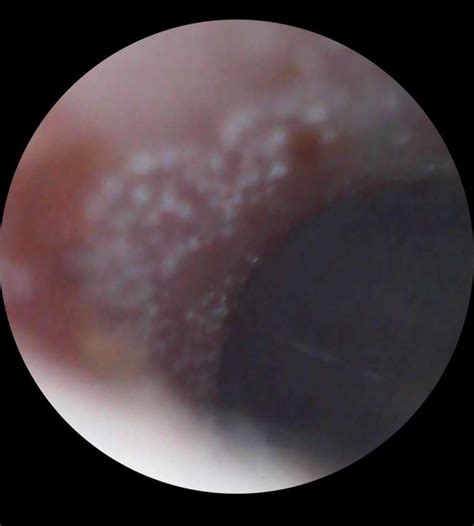

Many people wonder how to clean my ears safely, often turning to common household objects like cotton swabs, which experts frequently advise against. Understanding the purpose of earwax—scientifically known as cerumen—is the first step toward better ear health. Far from being "dirty," earwax is a natural, protective substance produced by your body to trap dust, bacteria, and other foreign particles, preventing them from damaging the delicate structures of your ear canal. Under normal circumstances, your ears are self-cleaning; as you talk, chew, and move your jaw, old wax is naturally pushed out toward the ear opening, where it can be easily wiped away. However, some individuals produce excess wax or have narrow ear canals, leading to buildup that may require gentle intervention.

Before you attempt to remove wax, it is crucial to recognize the difference between normal accumulation and a genuine blockage. If your ear feels full, muffled, or you are experiencing mild hearing loss or discomfort, you may have an impacted wax plug. However, trying to "clean" ears that do not actually need it can lead to irritation, infection, or accidental damage to the eardrum. If you have a history of perforated eardrums, ear surgery, or currently have ear tubes, you should never attempt DIY cleaning methods and should consult an ENT specialist instead.

If you are wondering how to clean my ears without causing damage, focus on gentle, non-invasive techniques. The most recommended approach is to soften the wax first so it can naturally exit on its own. Using over-the-counter cerumenolytic drops (wax-softening drops) or a few drops of mineral oil, baby oil, or glycerin can help break down hardened wax. Lie on your side with the affected ear facing up, apply the drops, and let them sit for a few minutes before sitting up and allowing the fluid to drain onto a tissue. Repeat this process for two or three days.